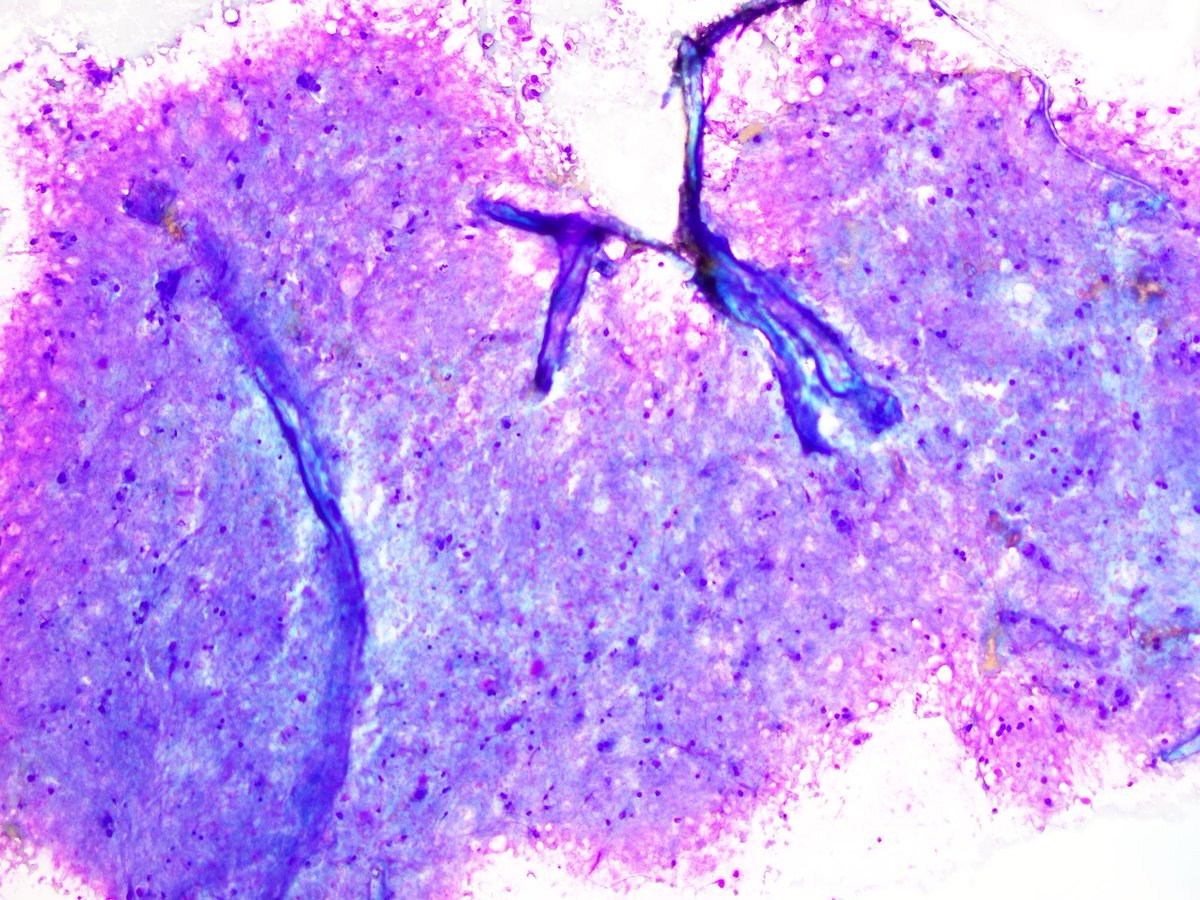

@pepeheffernan

3 days

Both patients underwent VENTRICULAR DERIVATION due to high intraventricular pressure, so these are CSF samples containg normal brain tissue fragments. I have found two similar images on the web. Unusual cases, aren't they? Thanks! https://t.co/bwNVLM905x https://t.co/8kJvORVGgD